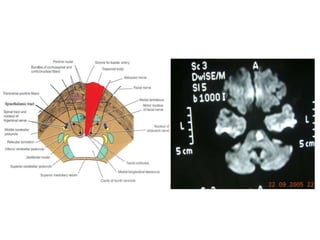

Medulla

Lateral medullary syndrome

(Wallenberg Syndrome – PICA occlusion)

A. IPSILATERAL

1.Xth cranial nerve palsy

2.Cerebellar signs

3.Horner’s syndrome

4.Impaired pain, temperature

and touch on the upper

half of face

B. CONTRA LATERAL

Medial medullary syndrome –

Anterior Spinal Artery occlusion

A.IPSILATERAL

1.XIIth nerve palsy

B.CONTRALATERAL

1.Hemiplegia – sparing the

face

2.Hemianaesthesia sparing the

face.